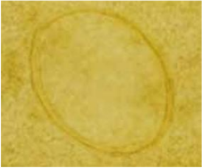

hookworm egg

Ancylostoma duodenale

Necator americanus